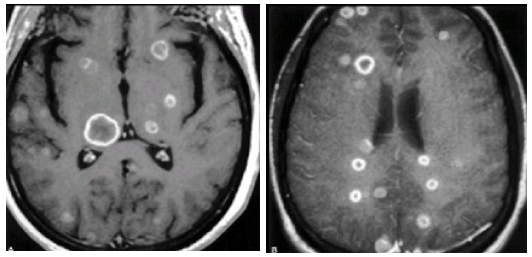

Sign: They are summarized in (Table 8 & Table 9 ). CT Scan: This was done for all the patients, 9 of them without I.V contrast, and 16 of them with I.V. contrast enhancement. Ten patients (40%) have single brain metastases, and 15 patients (60%) have multiple brain metastases Fig.(3.6) .In the 10 patients having single brain metastasis, the location [24,25] of the metastasis in relation to the brain was shown in (Table 10 ) and the relation of the primary origin of the tumor to multiplicity is seen in (Table 11 ). The density of the tumors was variable. 21 patients (84%) have solid tumors, and 4 patients (16%) have a cystic component of the tumor . The density of the solid tumors was isodense in 9 patients, hypodense in 7 patients, mixed density in 2 patients, and hyperdense in 3 patients

Enhancement of the tumor was seen in all the 16 patients in whom an I. V. contrast was used. 6 patients (37.5 %) showed ring like enhancement and 10 patients (62.5 %) showed heterogeneous enhancement.Perifocal edema was noticed in all the cases. It was marked in 6 patients (24 %), moderate in 15 patients (60%), and mild in 4 patients (16%). The metastases were supratentorial in 14 patients (56 %), infratentorial in 5 patients (20%), and both supraand [26,27,28] infratentorial in 6 patients (24%). Hydrocephalus was seen in 5 patients (20%), all of them have an infratentorial brain metastasis. It was due to compression of the 4thventricle by the metastasis leading to dilatation of the lateral and 3rd ventricles (triventricular hydrocephalus) (Figure 6 ).

MRI: This was done for only 11 cases according the availability of this study in these hospitals. T1 and T2 studies done for all of those taken the MRI study but Gadolinium contrast study done for only 5 of those cases. (Figure 7& Figure 8 ) Brain MRI T1 and T2 studies

Dysphasia was present in 8% of our patients, which is comparable to other studies that record it in 10% of their patients. It was a good localizing sign in our study. CT Scan of the brain showed that 60%of our patients have multiple brain metastases which is comparable to the 51% recorded by [54,55] study20, but is still lower than that recorded by studies that depend on the autopsies of the died cancer patients that record multiplicity in 60-85% of the patients.24 This percentage will also be higher by the more use of other sophisticated investigations such as the MRI. In comparing the distribution of the metastases in the brain of our study and [56]study we will find the following: Parietal 30%versus 19% frontoparietal 20% versus 7%; parietoccipital 20% versus 19%, cerebellum 10% versus 15%.So in this study about 70% of the metastatic lesions are in and around the parietal lobe compared to 48% in the study20 and this is due to the fact that most of the metastatic emboli reach the brain through the middle cerebral artery and its branches. The CT scan results of our study showed that 71.4% of the metastases from lung origin were multiple, while for the metastases of breast origin 80% were single

The same results were obtained by the study but with different percentages in which 54% of lung metastases were multiple and 68% of breast metaslascs were single. 61% of out¬patients have a supratentorial lesion, which is less than the 80% recorded by other series. [57] This is because we have included those patients with single metastasis and not those with multiple metastases like the other studies. The infratentorial metastases account for 32% of the patients, which is comparable to other series 20 that reported it in 15% of the patients. The other findings of the CT scan were compared to those in study20 and they were consistent with brain metastases i.e. circumscribed parenchymatous lesion or lesions with a [58,59]cystic component in 16% of the patients; isodense, hyperdense or hypodense; enhancing after contrast infusion in a heterogeneous fashion (62.5%) or ring-like enhancement (37.5%); with mild-severe surrounding edema and edema is more marked with multiple melastases, that cause a mass effect on the adjacent structures and ventricular system causing hydrocephalus in 20% of the patients[60,61].